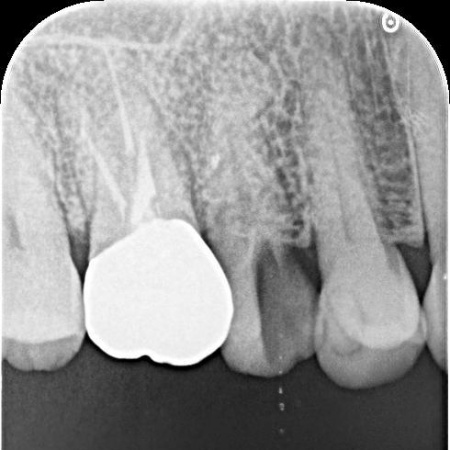

| 診断 | レントゲン撮影をして詳しく拝見したところ、右上奥歯の頭部分「歯冠」が縦に割れる「歯冠の垂直破折」が確認できました。 割れ目が深い場合は、歯の温存が困難です。 今回の症例では、症状や割れ方に応じて治療方針を慎重に判断する必要があると診断しました。 |

治療前

治療中